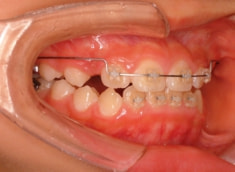

治療後(1年3ヶ月後)

治療法:上顎拡大装置+フルパッシブブラケット(クリアスナップ)+フェイスマスク等

治療期間:1年3ヶ月